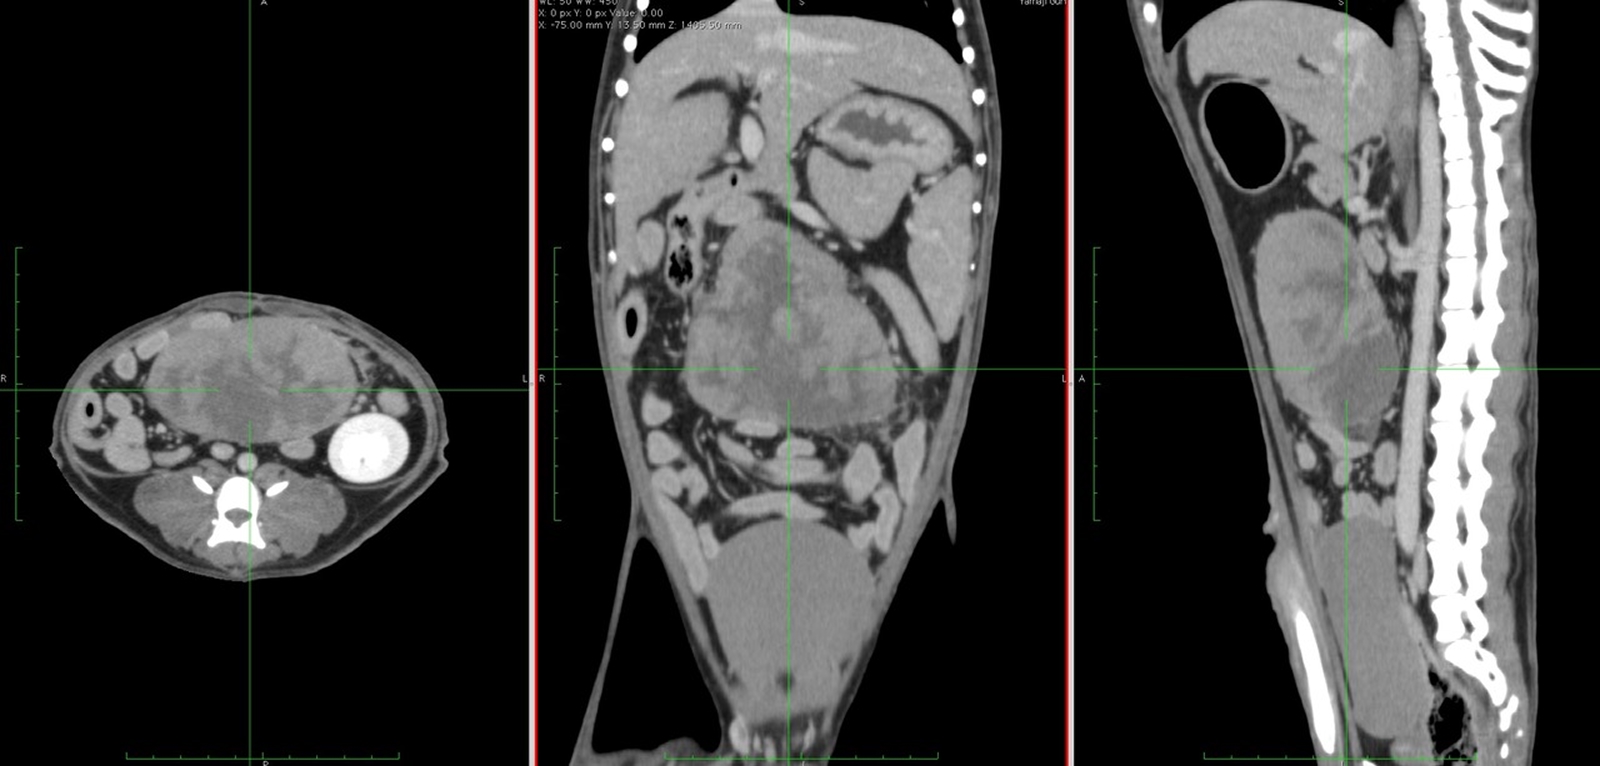

0.5ミリメートルの間隔で断層輪切り画像を作成 CTとは、Computed Tomography(コンピュータ断層撮影)の略です。

0.5ミリメートルの間隔で断層の輪切り画像を作成できるため、ごく小さい病変も描出可能です。

造影剤を使用することにより、腫瘍などの病変部位がわかりやすくなり、腫瘍付近の血管を把握することも可能です。

CTは、0.5ミリメートルの間隔で断層画像を輪切り画像が作成できるため、ごく小さい病変も描出可能です。